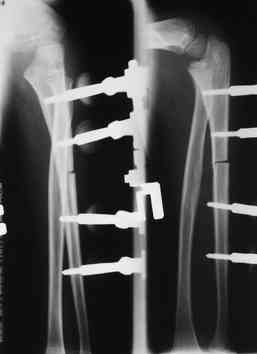

Артротомия, иссечение рубцов, остатков кольцевидной связки. На проксимальный отдел локтевой кости стержневой аппарат (рекомендуют

Compact II выпущеный Stryker Howmedica, но за неименеем...), остеотомия проксимального отдела локтевой кости, вправление головки лучевой кости, замыкание аппарата, проверка стабильности головки

У нас были проблемы. Скорее всего связанные с использованием стержневого аппарата с простым соединением. В Компакте же скорее всего шарнирное, со свободой движения во всех плоскостях, что конечно, значительно должно упрощать фиксацию в правильном положении.

1 подвывих головки лучевой кости в положении супинации - через 2 недели после операции- под ЭОП: аппарат разблокирован, повторное вправление головки, стабилизация аппарата.

2 По снятии аппарата через 2 мес после операции рефрактура в месте остеотомии(на фоне активного ротационного движения)- под контролем ЭОП выполнен

интрамедуллярный остеосинтез TEN. Положение головки луча стабильное.